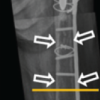

Surgery was performed under spinal anesthesia and tourniquet control. The knee was exposed through the previous incision, with the fractured tibial tuberosity everted laterally, taking care not to breach the lateral periosteum of the tuberosity. The loose implant was removed, and the bone stock was assessed. It was found that the posteromedial half of the tibial plateau was intact, and the tibial component had lifted off at the cement-implant interface. The anterolateral tibial plateau was compressed, but the lateral periosteal sleeve remained intact and attached to the laterally displaced fragment of the tibial plateau (Fig. 2, 3). At this stage, tibial stem preparation began, as a tibial stem was necessary regardless of the final approach. After adequate reaming, the stemmed tibial trial was implanted, seating it on the preserved medial tibial condyle. A trial reduction was performed, and the knee was taken through its full range of motion to assess the integrity of the collateral ligaments and the stability of the knee joint. The rotation of the tibial implant was determined by the preexisting tibial keel flange mark on the medial tibial condyle. Once the knee was confirmed to be stable, the next step was to address the bone loss, either with a metaphyseal cone or bone graft. Given the retained bone stock and pre-operative X-rays, it was determined that preparing for a metaphyseal cone would further erode the medial half of the intact tibial plateau, thereby reducing bone stock. Moreover, placing the lateral tibial plateau bone and tibial tuberosity in opposition to the metallic material of the metaphyseal cone could compromise the healing potential of these fragments with the native tibial bone. Therefore, the final decision was made to rebuild the lateral tibial plateau with bone grafts. A tricortical bone graft was harvested from the ipsilateral iliac crest and shaped into smaller pieces after measuring the depth of the bony defects at different levels on the tibial plateau. A minimal revision cut was made on the tibia to freshen the medial condyle bone for better cementing. Multiple pieces of tricortical bone graft were grafted onto the tibial plateau to rebuild the bone stock (Fig. 4). Gentle tapping over the grafted bone was done by placing the base plate over the tibia to level the grafted bone. Three cerclage wires were looped around the stem of the tibial component, and the final cemented tibial component was implanted (Fig. 5). A trial reduction was performed, and an 11 mm tibial insert was chosen after satisfactory trialing. The lateral end of the cerclage wires was passed through the lateral periosteal sleeve of the tibial tuberosity and tied to the medial ends over the tuberosity after reducing it onto the tibia. The wound was closed in layers over a suction drain, and a post-operative knee brace was applied for 3 weeks. The patient was advised to perform static quadriceps strengthening exercises and calf-pumping exercises from day one. Passive-assisted knee flexion up to 60° was recommended for the first 3 weeks, gradually progressing to 90° over the next 3 weeks. She was kept non-weight-bearing for 4 weeks, followed by partial weight-bearing for the next 6 weeks. The patient was followed up at 1 month, 3 months, 6 months, 1 year, and yearly thereafter. Radiological examinations were performed at each visit, confirming radiological union with good osteointegration of the graft at 6 months (Fig. 6). At 1-year follow-up, the patient regained a range of motion of 0–110°, which was 10° < the opposite knee (Figs. 7, 8). Oxford knee score used to evaluate the functional outcome of the operated knee came out to be 42 compared to 46 on the opposite knee (best outcome score=48).